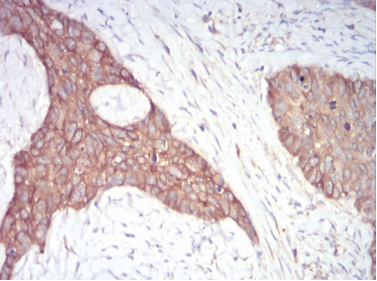

IHC    1/200 - 1/1000